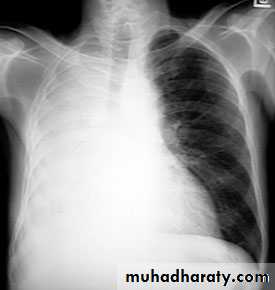

Complete rt. & left Lung collapse